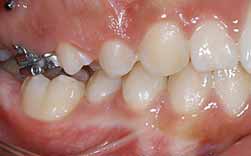

A principal causa de falta de espaço para a erupção de um molar definitivo é a perda precoce de um molar decíduo.

Aquele que provoca maior e mais rápida perda é o segundo molar decíduo superior, seguido do segundo molares decíduo inferior.

Quando a perda já se verifica e o exames demonstram a existência de falta de espaço para a erupção dever-se-à recorrer a um dispositivo apropriado para a recuperação do mesmo.